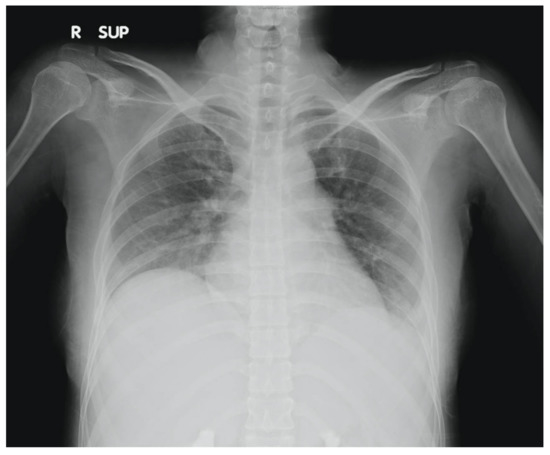

Our patient, a 28-year-old lady with no prior medical illnesses, presented to our ED with a one-day history of persistent, diffuse, dull abdominal pain associated with nausea, vomiting, and watery stools. Physical examination revealed that she was tachycardic (pulse rate 115 beats/min) and slightly hypertensive (systolic blood pressure 143 mmHg), but otherwise not tachypneic nor febrile. There was generalised abdominal tenderness without any rebound tenderness. Laboratory investigations demonstrated leukocytosis with neutrophilia (white cell count 16 × 109/µL, neutrophils 86.2%) and elevated levels of C-reactive protein (21.1 mg/dL). Other blood parameters were normal. Chest X-ray found mild left pleural effusion (Figure 1). The patient was initially treated for the provisional diagnosis of infectious gastroenteritis and colitis with empirical antibiotic therapy, but her symptoms of abdominal distension and pain continued to worsen.

Figure 1.

Chest X-ray of patient showing mild left pleural effusion.